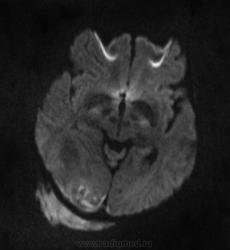

Мужчина проходит курс химиотерапии по поводу Т-клеточной лимфомы с первичным поражением кишечника (гистологическая верификация). За последний месяц - появление множественных очагов в печени, а также необычных изменений в голове.

- бесформенное образование в мягких тканях затылочной области, накапливающее контраст;

- утолщение твердой мозговой оболочки в той же области с накоплением контраста по пахименингиальному типу;

- отек прилежащей мозговой ткани с геморрагическими изменениями в коре, сопровождающийся масс-эффектом.

Мое мнение это лимфома кожи с прорастанием (если так можно сказать) через перфорирующие сосуды в ТМО, с кровоизлияниями в коре за счет повреждения сосудов. Либо это лептоменингальнаые проявления лимфомы. Больше на ум ние чего не приходит. Хотелось бы услышать мнение более опытных специалистов. но все почему-то молчат...

Я тоже думаю, что это лимфома. Думаю, не так важно, прорастает ли она из мягких тканей в мозговые оболочки, или наоборот. Только поражение мозговой оболочки - это пахи-, а не лептоменингиальные изменения.

В таком случае изменения в мозговой ткани - это отек, обусловленный нарушением венозного оттока по поверхностным венам; думаю, вкупе с геморрагическими изменениями этот отек можно квалифицировать как венозный инфаркт.